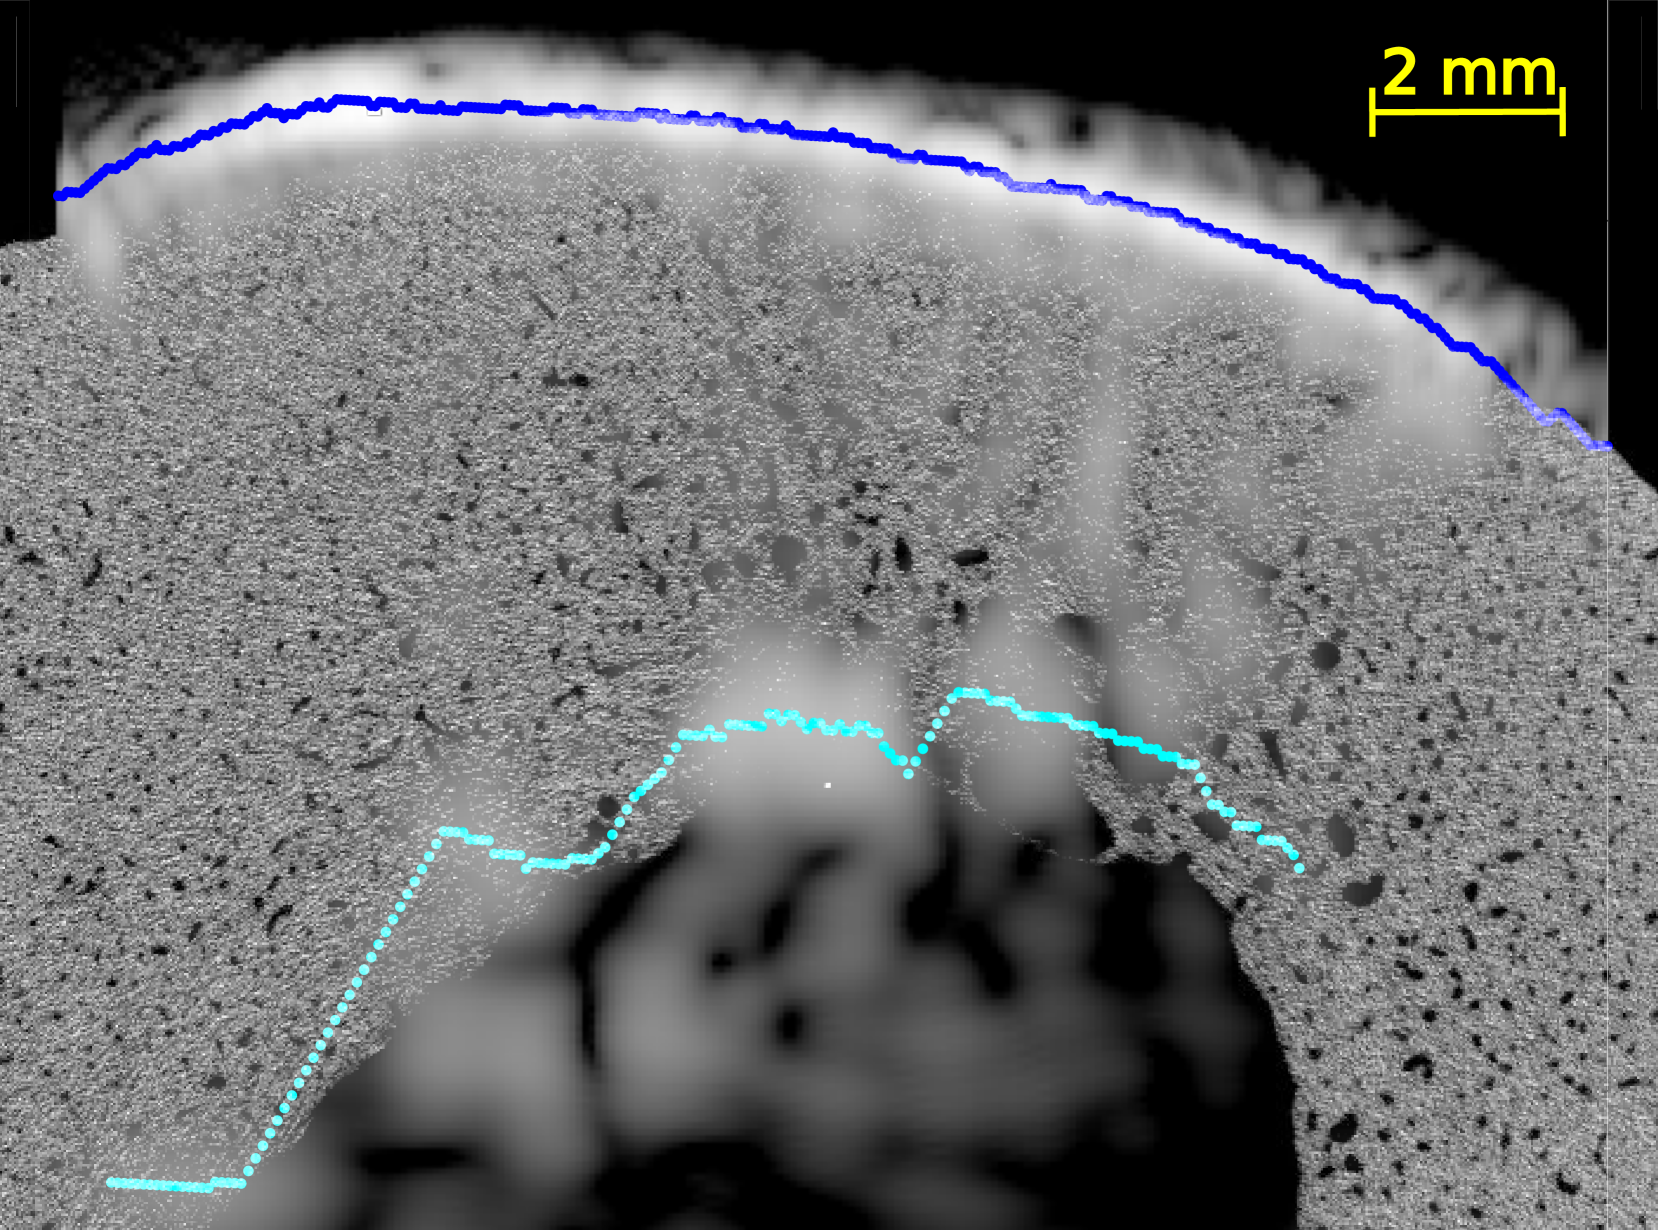

In all US images (Figure 4 and Figures S2-5 of supplementary materials), the periosteal surface appeared as a very bright line. The brightness of the endosteal surface was found to decrease with increasing porosity and with the presence of large pores. The endosteal surface was relatively bright in Samples 1 and 2 which had a small number of large pores and a small porosity; while the contrast of the endosteal surface was relatively weak in Samples 3 and 5 which had a higher porosity and some large pores near the endosteal surface (see the HR-µCT images (panels (a), (d), (g) and (j) of Figure 4). Segmentation with Dijkstra’s algorithm successfully delineated periosteal and endosteal surfaces for all measurement zones in all samples (see Figure 4). US images were aligned on HR-µCT images based on the periosteal surface segmentation. Periosteal surfaces from the US images accurately matched the periosteal surfaces segmented from the HR-µCT images: for all VOIs and all measurement repetitions, the root mean square error (RMSE) between the two segmentations was smaller than 0.3 mm, which value corresponds to half a US wavelength in water at 2.5 MHz (i.e., approximately the resolution limit).

We observed a good match between the segmented endosteal surface in the US image and the boundary of the cortex as seen in the HR-µCT image. The segmented endosteal surface closely followed the shape of the bone in the samples 1 and 2 which were the less porous and less heterogeneous. It is noteworthy that, despite the large thickness and complex geometry of sample 2, the endosteal surface was very bright in the US image. In the more porous and heterogeneous samples 3 and 5, the segmented endosteal surface followed the gross shape of the bone but was inside the cortex as seen in the HR-µCT image, above some large pores found close to the endosteal cortex boundary.

We evaluated the quality of US anatomical reconstructions and wave speed measurements across sixteen VOIs from bones of four individuals. Indeed, the bone of a fifth individual (sample 4) was too porous and heterogeneous to be effectively imaged through US. Our results indicate that the cortex boundaries and cortical thickness can be accurately determined for homogeneous and moderately porous VOIs, even for a thick cortex, as observed in samples 1 and 2 (mean thickness 2.9 and 5.9 mm and porosity between 5.0 and 12.3%, respectively). In these cases, the overlaying of US and HR-CT images showed that the segmentation of the surfaces in US images with the Dijkstra’s method closely aligns with the actual boundary, achieving thickness measurements with mean relative errors of 9 % and 4 %, respectively. In regions with higher porosity and larger pore diameters (samples 3 and 5 with porosity between 10.9 and 16.6% and Lg.Po.Dm between 224 and 307 m, respectively), the brightness of the endosteal surface is significantly reduced (from 7 dB to -5 dB). Nevertheless, Dijkstra’s algorithm was able to delineate endosteal boundaries that generally lied within the cortex, above the region with very large pores nearest to the endosteal surface. Consequently, in these cases, US-based cortical thickness measurements underestimated the reference (mean relative errors of 32 % and 47 %). However, for these highly remodeled bones with large resorption cavities leading to a trabecularization of the endosteal region, the delineation of the endosteal boundary as the end of the cortex and the beginning of the medullary canal is ambiguous, making it challenging to obtain a meaningful estimate of cortical thickness in the HR-CT images [5]. Another limiting factor in comparing cortical thicknesses determined from HR-CT and from US images lies in the slight differences in the regions of interest used for each VOI. The region of interest used for HR-CT images (Figure 2) were slightly larger than that used for US images. In the latter, as shown in Figure 4, the surfaces could only be reconstructed for a limited portion of the cortex due to the finite US probe aperture.

It is noteworthy that the inner cortex surface reconstructed with US was consistently within the bone, indicating that it effectively detects the most compact region corresponding to the tissue above the large pores in the endosteal region.

In highly porous samples exhibiting large pores, the reconstructed endosteal surface may show a reduced brightness and a lack of continuity. Indeed, previous simulations demonstrated that increased pore size has a strong detrimental effect on endosteal interface brightness [29], primarily due to the enhanced scattering by large pores. This ex vivo study corroborates these simulations results by providing an experimental proof that pore size is a major factor influencing intracortical US image quality.

In certain cases, such as sample 4 in this study, the US imaging method may fail to reveal the inner cortex surface on the reconstructed image. In an in vivo application of the method, such failure would strongly suggest that the bone has undergone excessive resorption and has very large pores. Consequently, the inability to visualize the endosteal surface could serve as a marker of an advanced alteration of the cortical bone tissue.